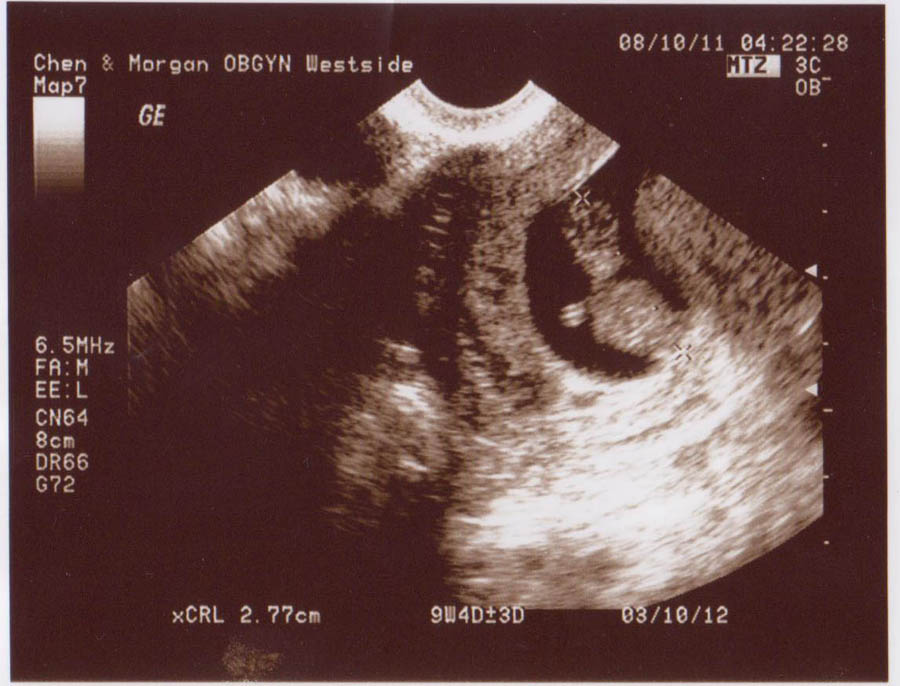

9 Weeks